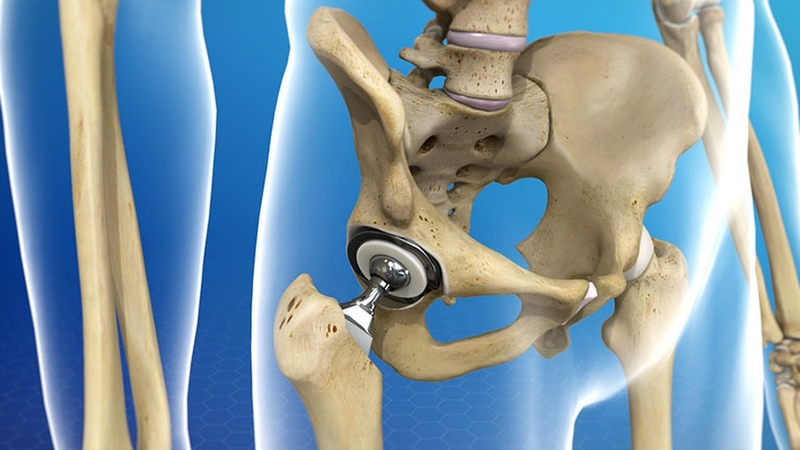

Phẫu thuật thay khớp háng được thực hiện để cắt bỏ khớp háng bị tổn thương và thay thế bằng khớp nhân tạo. Thông thường, phương pháp này chỉ được chỉ định đối với những trường hợp bị tổn thương khớp háng nghiêm trọng và không thể điều trị bảo tồn. Ở Việt Nam, kỹ thuật này đã phát triển được hơn 40 năm và đã có hàng nghìn ca bệnh được thay khớp háng thành công mỗi năm. Giúp người bệnh thoát khỏi đau và khó chịu, tái khôi phục khả năng vận động và mở ra cuộc sống mới.

Phẫu thuật thay khớp vùng háng được xem là một thành tựu to lớn trong lịch sử phát triển ngành chấn thương chỉnh hình. Kỹ thuật y khoa này thường được thực hiện ở những bệnh viện lớn với đội ngũ chuyên gia và thiết bị hiện đại, cho tỷ lệ thành công cao.